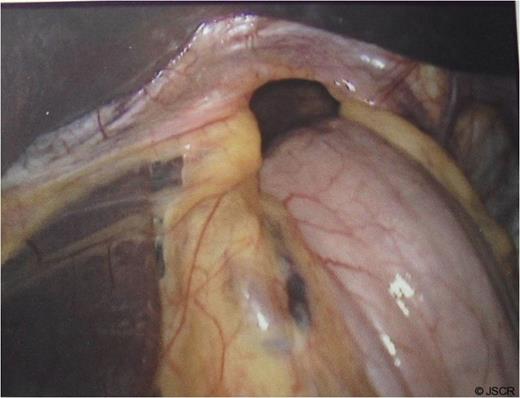

During the sac dissection, the patient developed tension pneumothorax due to an iatrogenic tear of the right pleura requiring a chest drain. He was closely observed in the high dependency unit with pain relief through PCA (morphine) and intravenous paracetamol and oral feeding commenced post-operatively. Arterial blood gas showed pO2 of 10.7 and PCO2 of 6.54 on 60% oxygen and an early post-operative chest x-ray revealed bilateral pulmonary infiltration (Fig. 3). Non-cardiogenic pulmonary oedema was suspected and the patient was started on 5mmHg pressure CPAP.

Early post-op chest x-ray showing patchy shadowing/ consolidation over the left side of chest